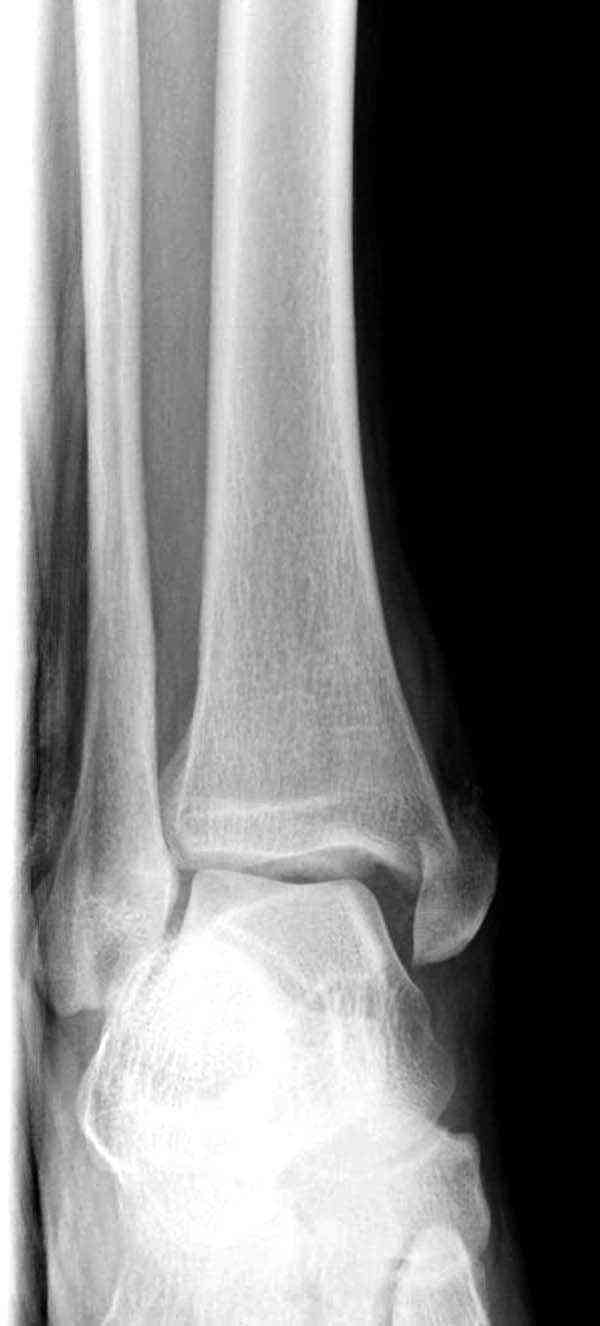

Случай прошлого года:пациентка-молодая ,крупная женщина ,30лет.Травма в начале апреля 2009г-пронационный перелом лодыжек с подвывихом стопы.Ко мне обратилась через 35 дней,прооперирована 22.05.2009г.Внутренняя лодыжка фиксирована по Веберу,наружная реконструктивной пластиной с наложением болта-стяжки.Иммобилизация "сапожок" в течении месяца,затем пригипсовано "стремя".Гипс снят 10.07.2009г

Достаточно быстрое восстановление функции.В октябре 2009г-почувствовала боль,в области рубца над гайкой открылся свищ.На Р-граммах-консолидация переломов и смещение гайки по стяжке.10.11.2009г-конструкции удалены,санация,заживление ран.В настоящее время пациентку ничего не беспокоит.На операции-раскручивание гайки-болталась на конце стяжки.Вопросы:какой механизм раскручивания и что я неправильно сделал?Свои версии:1)в области синдесмоза успела образоваться рубцовая ткань,которая при движении в суставе"пружинила",поскольку голеностопный сустав является спиральным, то и биомеханика подобна кривошипному механизму.2)Реконструктивная пластина не "реконструировалась" по форме лодыжки.Наложил,как есть.То есть подпружинивала сама пластина.Ну,это мои догадки.Что нужно,чтобы избегать впредь таких,пусть и не "страшных"осложнений:Рассверливать через лодыжку область синдесмоза?Ставить шайбу-гровер?Тщательно моделировать пластину?Прилагаю сравнительные снимки-сразу после операции и перед удалением конструкции.

Визуально никаких вопросов по репозиции не было.Да и на основании чего сомнения,что наружная лодыжка не полностью репонирована или прорезалась проволка ???Я не вижу...Снимок после репозиции справа.

Нет первичных снимков, перелом очень низкий и под большим сомнением диагноз разрыва синдесмоза. Медиальная сторона отрепонирована на "хорошо" и, по-видимому, прорезание проволоки произошло во время операции. Без снимков трудно судить о высоте малоберцовой, а лодыжка находится в варусе. Лагирование получилось, но возле тонких шурупов передне-задний шуруп выглядит немного тяжеловато.